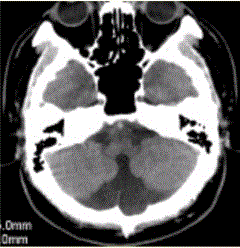

问题 男性,40岁。走路不稳数年。CT表现如下图。可能的诊断为

选项 A.神经纤维瘤病I型 B.Dandy-Walker综合征 C.结节性硬化 D.带状型灰质异位 E.颜面血管瘤综合征

答案 B